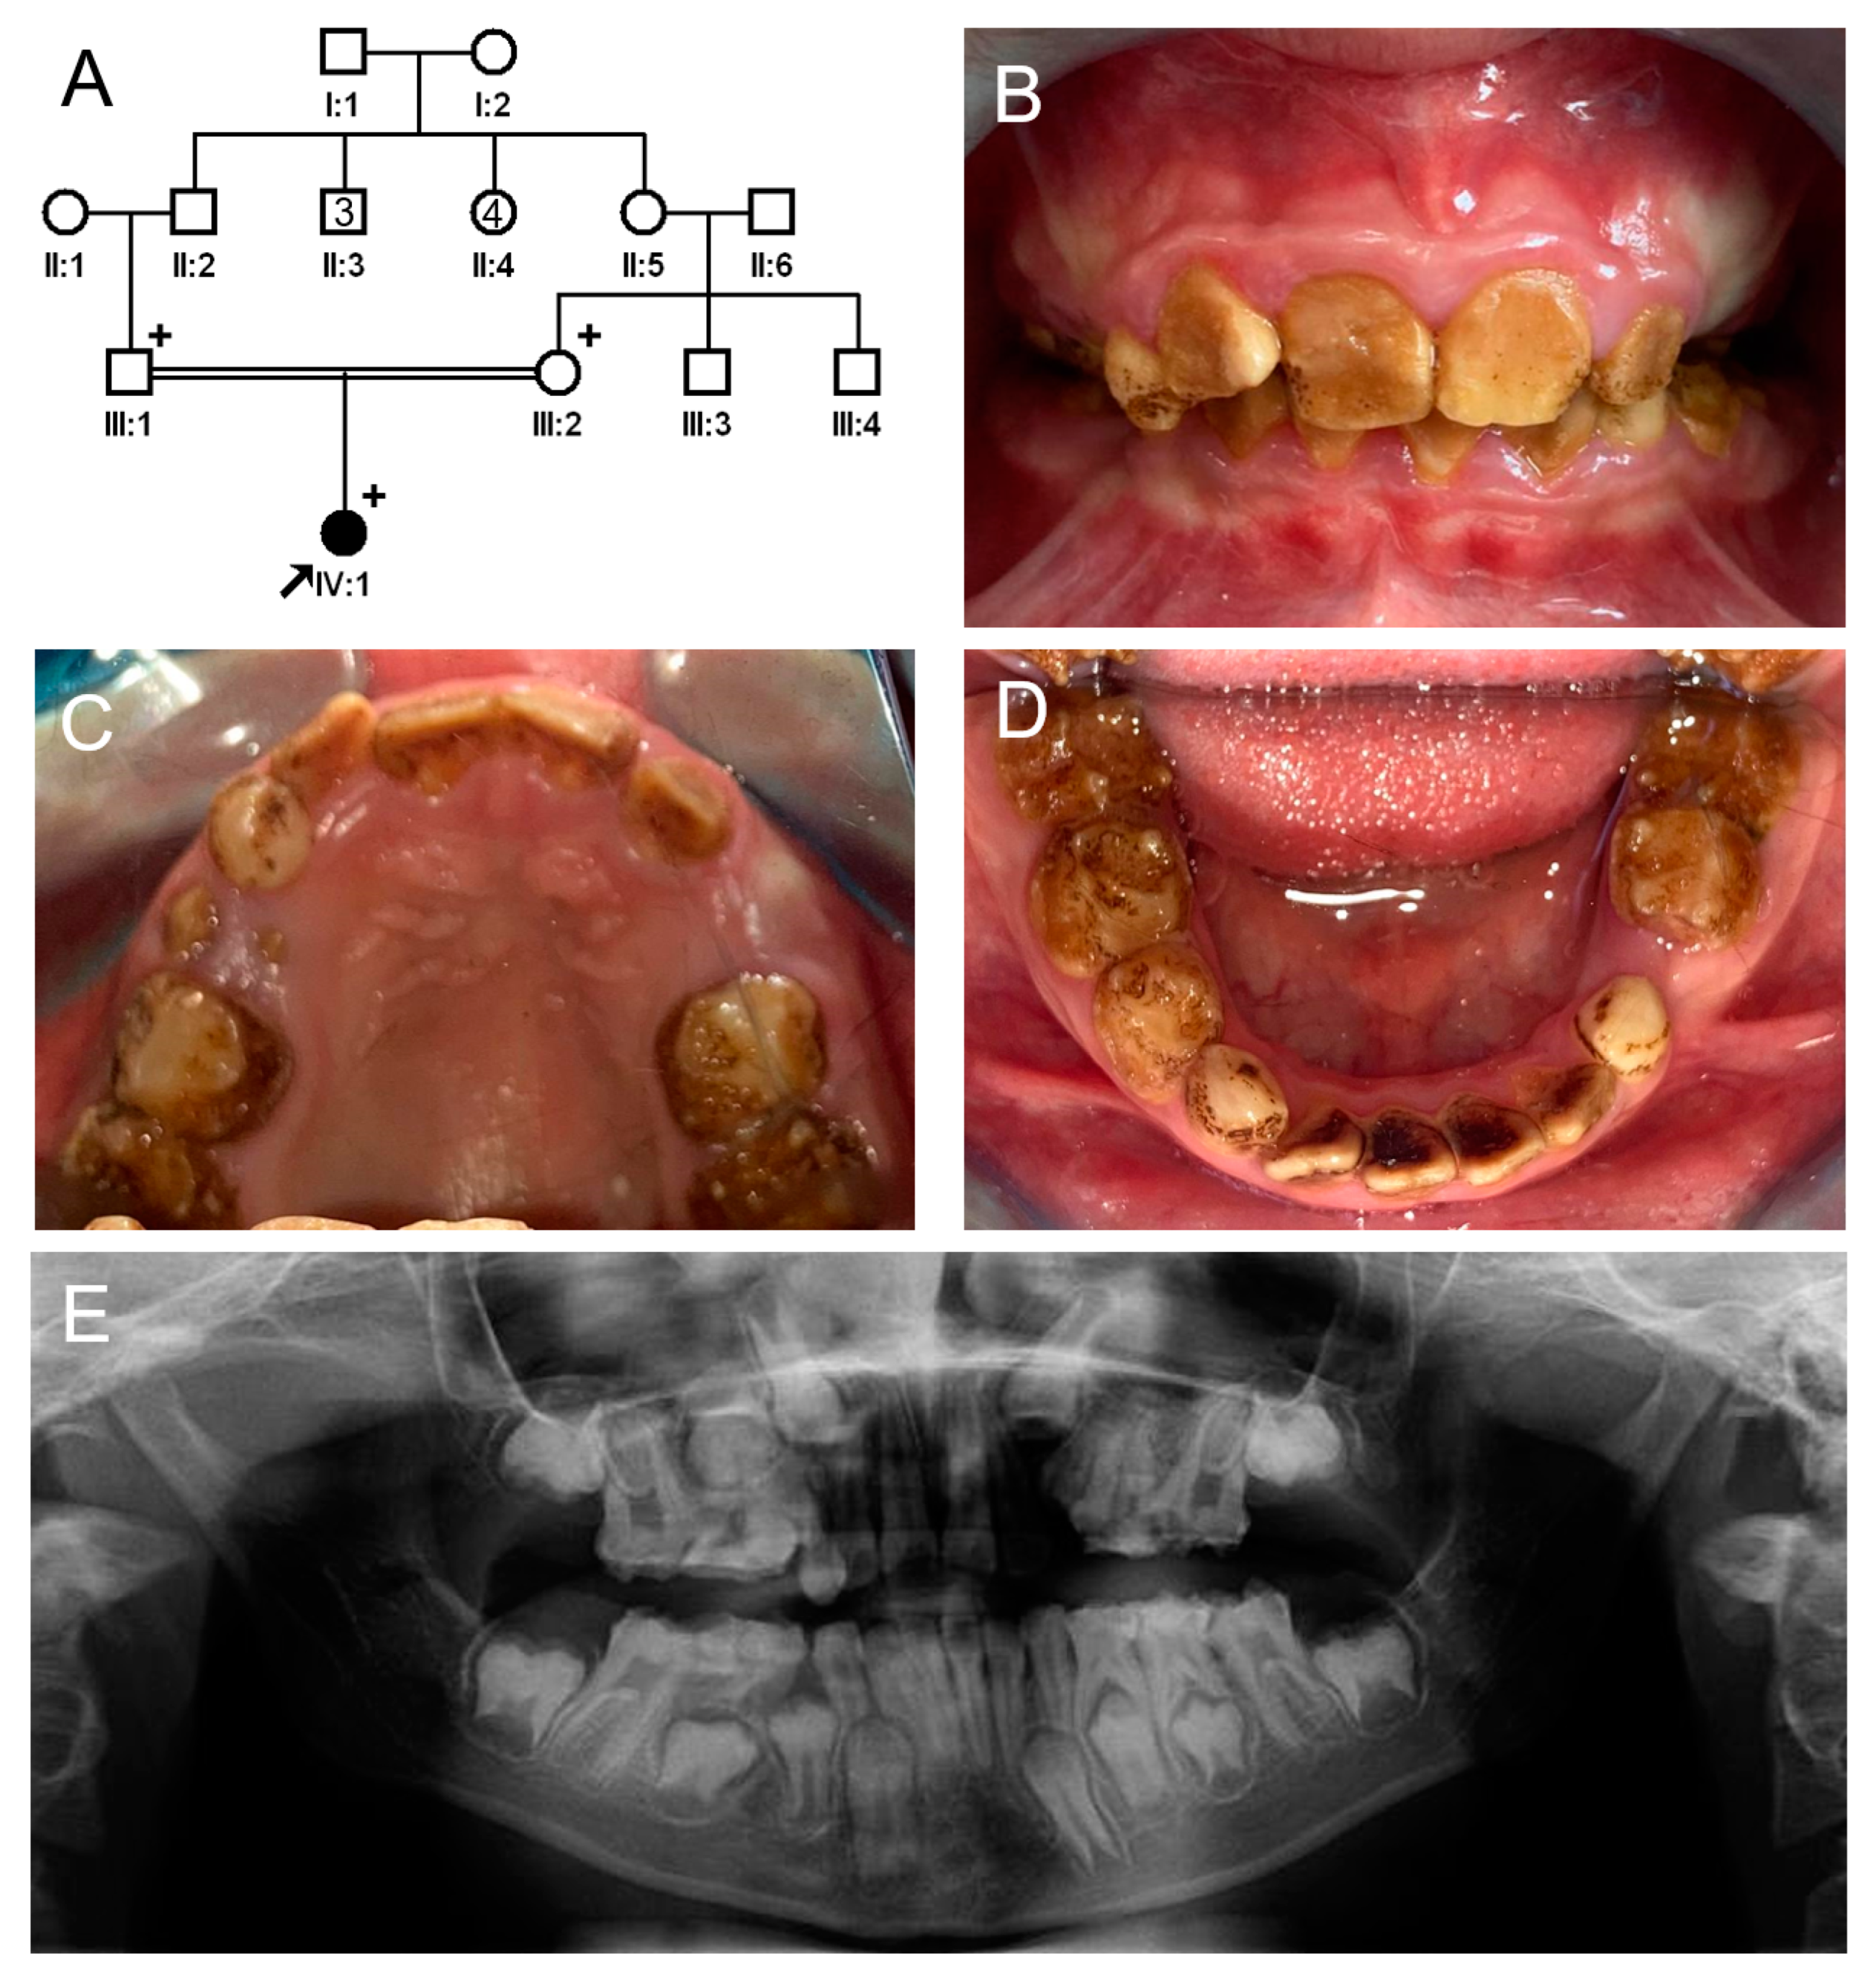

3.3. Family 3

The proband of family 3 was a 4-year-old female from a nonconsanguineous Caucasian family (Figure 5). She had no other remarkable past medical or dental history except for a generalized yellowish-brown discolored deciduous dentition. Her teeth showed attrition and enamel fractures mostly in the cuspal area. The remaining enamel barely contrasted with the underlying dentin, suggesting a reduced degree of mineralization. She was the only affected individual among her family members; therefore, a spontaneous or recessive mutation was suspected.

Figure 5.

Pedigree, clinical photo, and bitewing radiographs of family 3. (A) Pedigree of family 3. The black symbol indicates the affected individual, and the proband is indicated by a black arrow. A plus sign above the symbol indicates participating individuals. (B) Clinical photo of the proband at age 4 years. She has a dull yellowish-brown discoloration of her dentition, and the affected enamel shows attrition and fractures. (C,D) Bitewing radiographs of the proband at age 4 years show enamel fractures with reduced radiopacity.